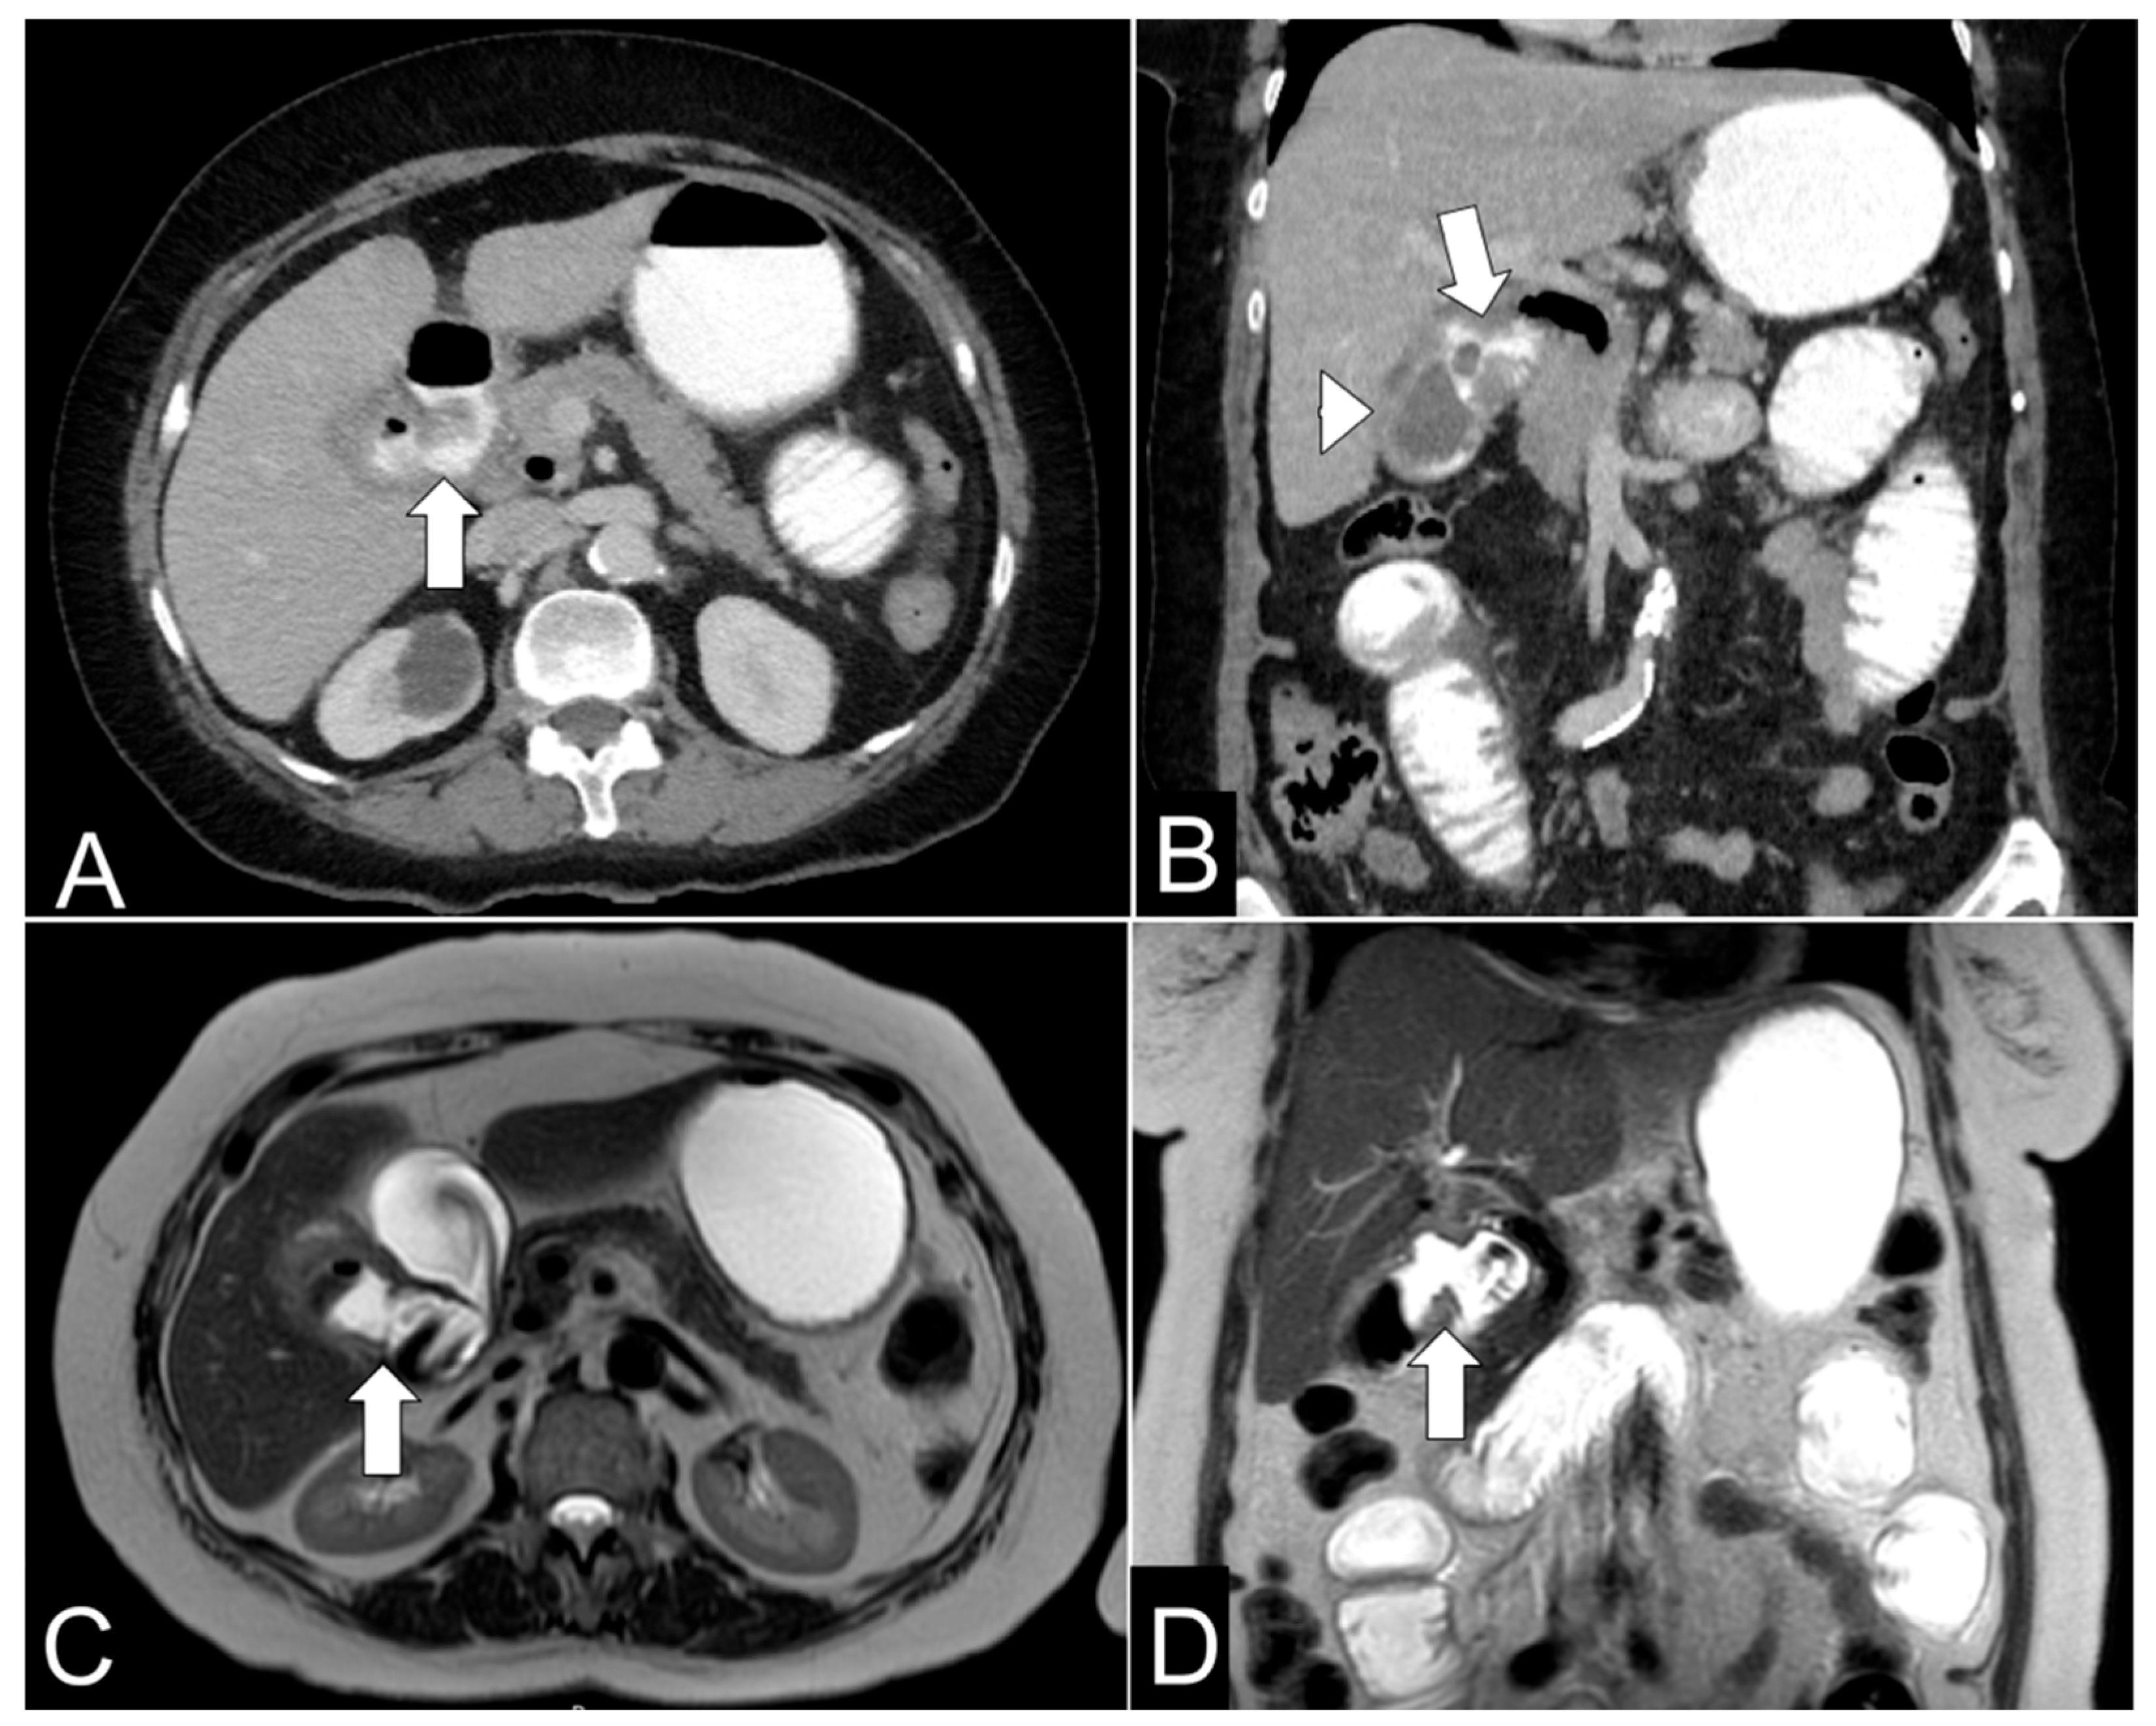

A total of four patients are presented in this case series. All the patients were in their eighth decade of their life and 75% were female. Regarding symptoms, all patients presented vomit and abdominal pain, however only one presented signs of acute abdomen. Vital signs only reported one patient with tachycardia and two with high blood pressure. Preoperative hemogram reported leukocytosis and neutrophilia in every patient, a high level of creatinine of one patient, and high glycemic levels in one patient. CT scans reported gallstones inside the intestinal tract (Figure 1) and cholecystoduodenal fistula (Figure 2) as findings. Every patient had an enterotomy as a surgical procedure. However, two patients had also a subtotal cholecystectomy. Surgical procedures also evidenced the presence of gallstones which were documented via photographs and removed (Figure 3). Evaluating complications, one patient had a surgical site infection, while the other was diagnosed with healthcare-related pneumonia. The other two patients did not present any complications. The average hospital stay was 9.5 days. One patient required treatment in the ICU (Table 1).

Figure 2.

(A) Axial contrast-enhanced abdominal CT scan showing a cholecystoduodenal fistula (arrow) with pneumobilia and passage of oral contrast into the gallbladder. (B) Coronal contrast-enhanced abdominal CT scan demonstrating a cholecystoduodenal fistula (arrow) with oral contrast passage into the gallbladder and cholelithiasis (arrowhead). (C) Axial T2-weighted MR cholangiography showing a cholecystoduodenal fistula (arrow) with pneumobilia. (D) Coronal T2-weighted MR cholangiography depicting a cholecystoduodenal fistula (arrow) with pneumobilia and cholelithiasis.